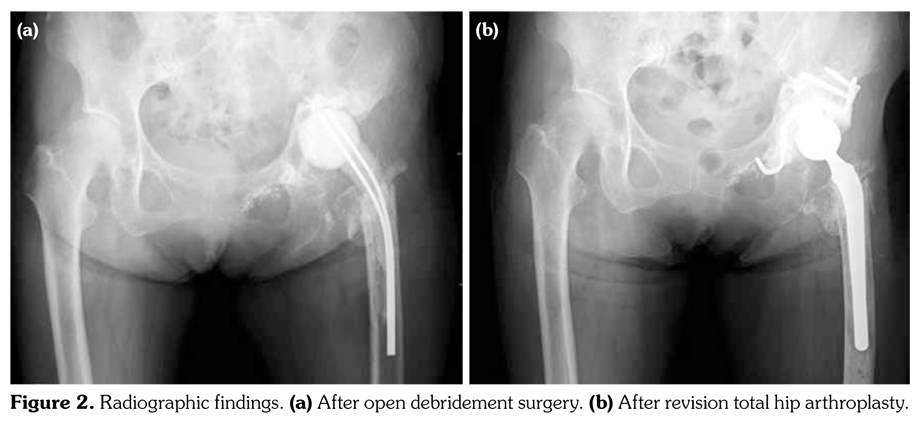

Case 2– A 62-year-old female with RA (Steinbrocker classification: functional class III, stage of disease progression 4) since 1989 was treated with non-biological disease-modifying antirheumatic drugs. Methotrexate therapy was started in 2000. However, methotrexate therapy caused interstitial pneumonitis in 2003. Therefore, we stopped methotrexate therapy, and changed the treatment with biological drug. Etanercept therapy (25 mg/week) was started in 2003. Patient underwent left THA in 2006. Etanercept therapy was discontinued for four weeks prior to THA, and restarted four weeks after THA. However, at postoperative fourth year, patient presented again with complaints of left hip pain accompanied by elevated levels of inflammation markers on laboratory examination [CRP, 8.6 mg/L (normal value; 0-0.3); white blood cells, 12,200 cell/mm(3) (normal value; 3,500-9,000)]. Methicillin-resistant Staphylococcus aureus was detected in culture of joint aspiration. Open debridement was performed immediately. Vancomycin had antibiotic sensitivity. Therefore, vancomycin was administered for six weeks. Administration dose of vancomycin was adjusted by therapeutic drug monitoring (peakto- trough concentration: 10-20 μg/mL). After the end of treatment, tacrolimus (2 mg/day) and prednisolone (5 mg/day) were introduced for the treatment of RA. Progression of RA increased in 2012, and etanercept therapy (25 mg/week) was introduced once again. After two months, patient suddenly presented with complaints of left hip pain accompanied by elevated levels of inflammation markers on laboratory examination (CRP, 3.8 mg/L; white blood cells, 10,800 cells/mm3). Methicillinresistant Staphylococcus aureus was detected in culture of joint aspiration. Immediately, open debridement was performed, prosthesis was removed, antibiotic-impregnated, cement spacer was inserted, and vancomycin was administered for six weeks (Figure 2a). Following conclusion of the treatment, revision THA was performed which reduced progression of the infection (Figure 2b). Tacrolimus (4 mg/day) with prednisolone (5 mg/day) was introduced for the treatment of RA after THA, and the patient had improved findings at follow-up (CRP <0.3 mg/L).